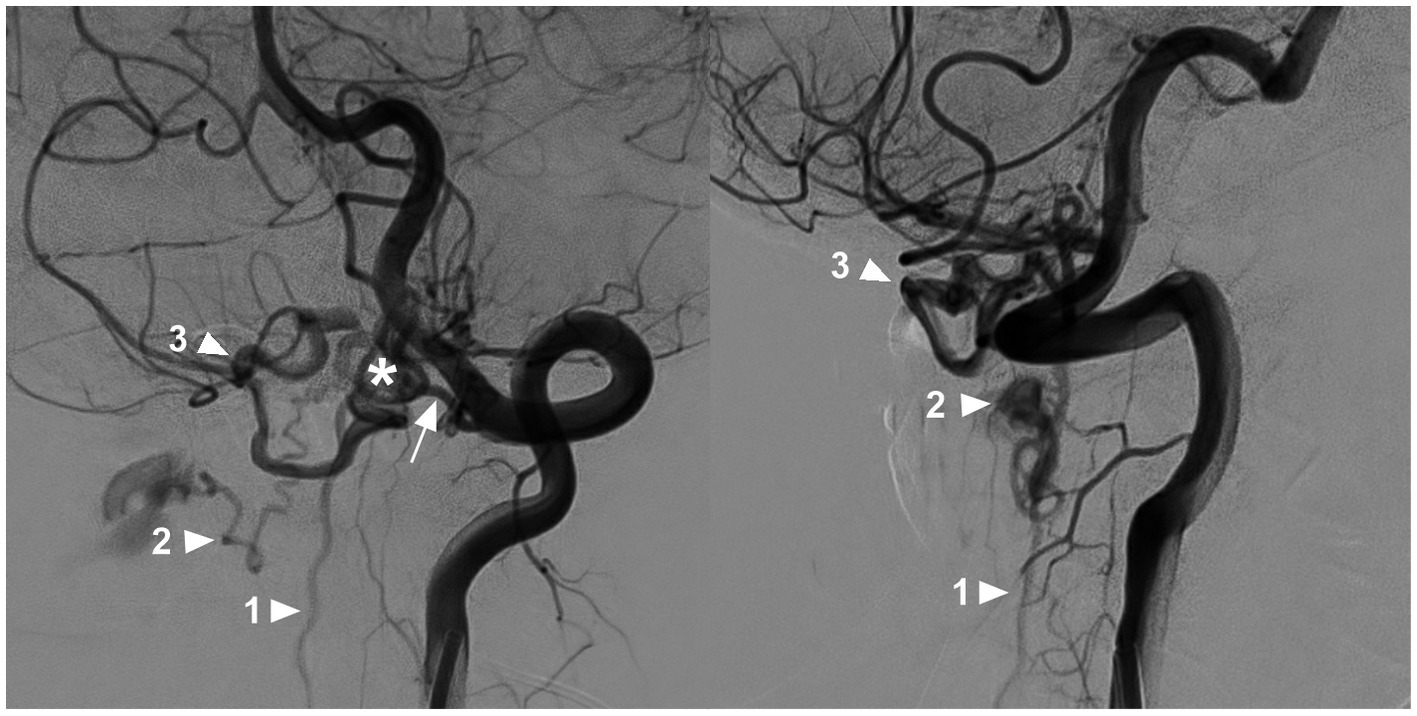

Most CCJ AVFs had intradural venous drainage, which was ventral to the medulla oblongata or spinal cord (9). Normally, venous drainage of the upper cervical cord flows downward to reach the outlet along the adjacent nerve root by bridging and radicular veins into the lateral epidural venous plexus. When CCJ AVFs occur, due to high hemodynamic pressure, draining veins may extend downward very far, even as far as the thoracic or sacral levels, to reach the outlet (63). High cervical CCJ AVFs also had upward intradural drainage. Even the draining veins can reflux upward into the intracranial venous system due to rich anastomosis (3, 4, 10, 36, 44, 55, 58, 61, 64). Due to the overload of the draining vein, drainage may involve multiple veins or multiple pathways (Figure 7) (33).

Figure 7

Multiple draining pathways in a high cervical CCJ AVF. Oblique-view DSA of the VA showing a CCJ AVF (asterisk in left panel) supplied by the C1 radicular artery (arrow in left panel); the drainage of the AVF had three pathways: downward into the perimedullary vein (arrowhead with number 1), lateral into the epidural venous plexus (arrowhead with number 2), and upward into the intracranial vein (arrowhead with number 3). AVF, arteriovenous fistula; C1, first cervical vertebrae; CCJ, craniocervical junction; DSA, digital subtracted angiography; VA, vertebral artery.

The drainage pattern of CCJ AVFs determines their clinical manifestation. CCJ AVFs with downward drainage mainly result in congestive myelopathy (Figure 8), whereas those with upward drainage usually result in hemorrhage due to draining vein rupture (Figures 9, 10) (4, 65, 66). In addition, increased hemodynamic stress may lead to varices of the draining veins in nearly 80% of high cervical CCJ AVFs (36, 53, 55).